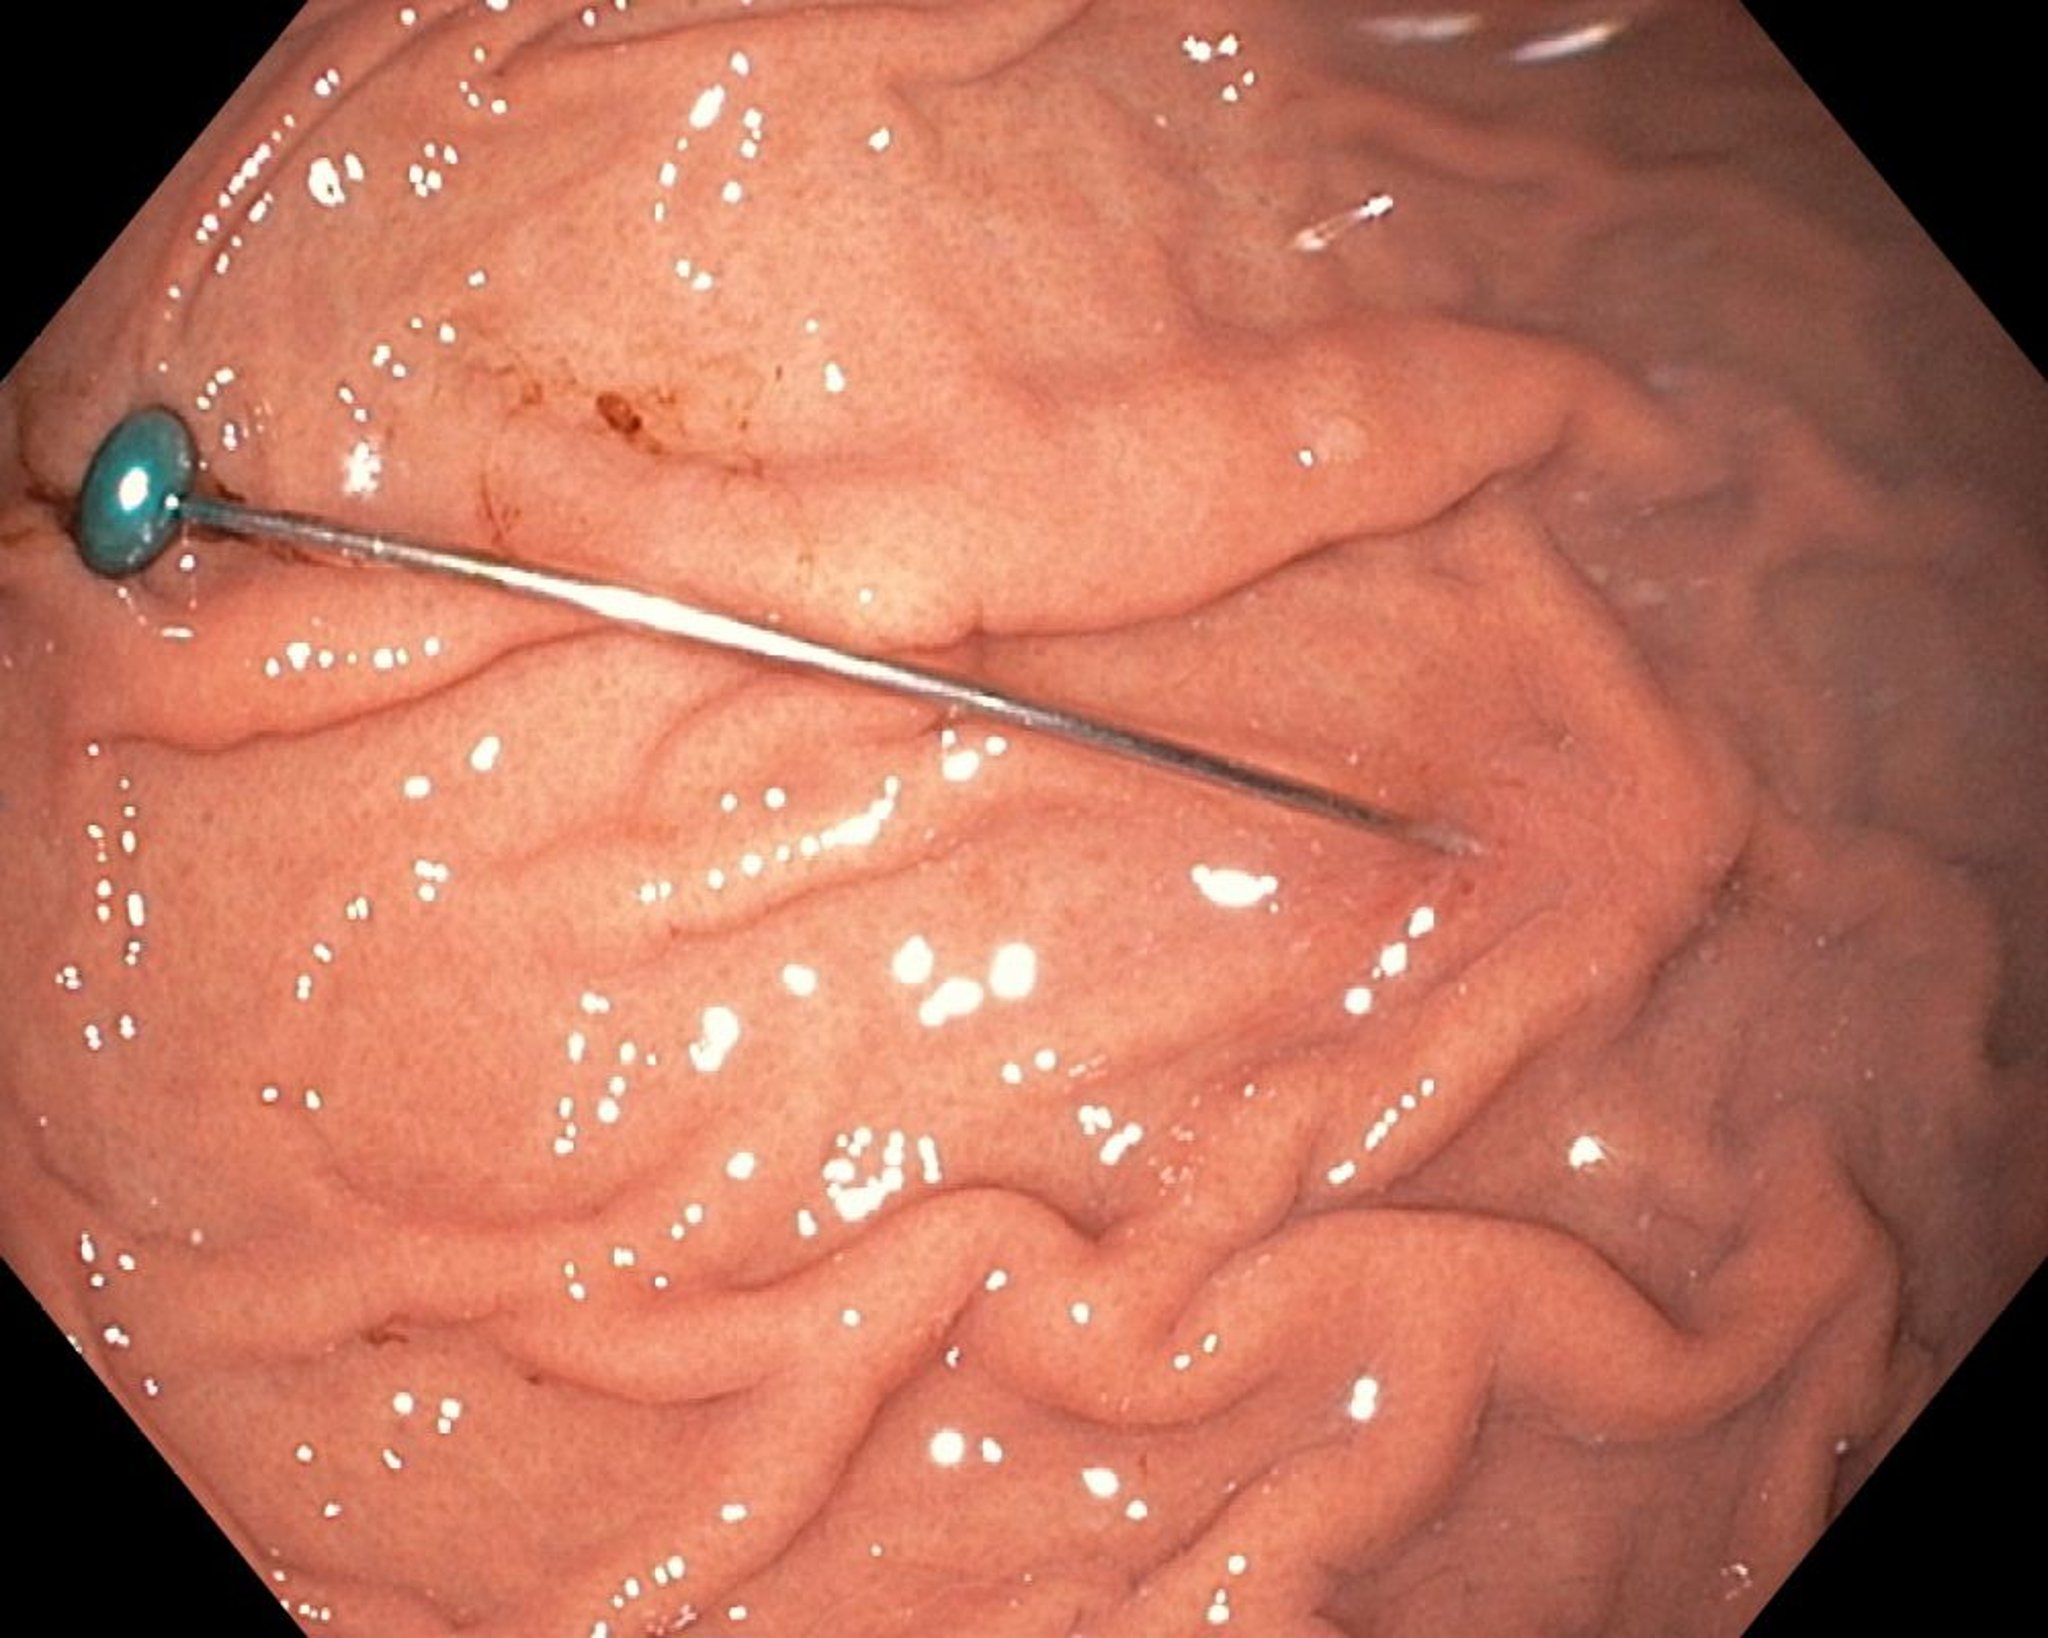

Corps étranger pointu dans l’estomac (endoscopie)

Cette image montre un corps étranger pointu dans l’estomac.

Image fournie par Dr Uday Shankar.